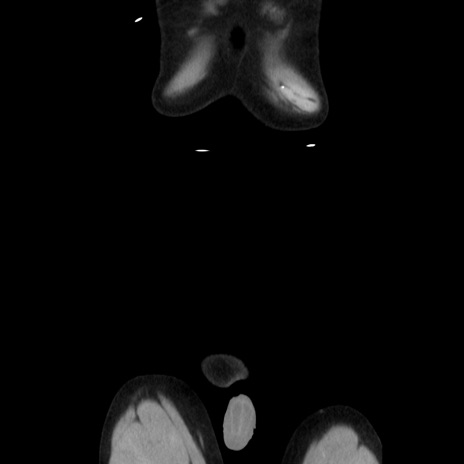

横断像

【症例】40歳代 男性

【主訴】腹痛

【現病歴】4時間ほど前に電車に乗車中に臍部上より腹痛出現。徐々に増悪し起立困難となり、救急外来受診。生ものは数日食べていない。今朝お雑煮を食べた。

【身体所見】BT 36.8℃、BP 117/84mmHg、HR 91/min、SpO2 97%、苦悶様、腹部:臍上部広範囲圧痛あり、反跳痛±

【データ】WBC 8100、CRP 0.03